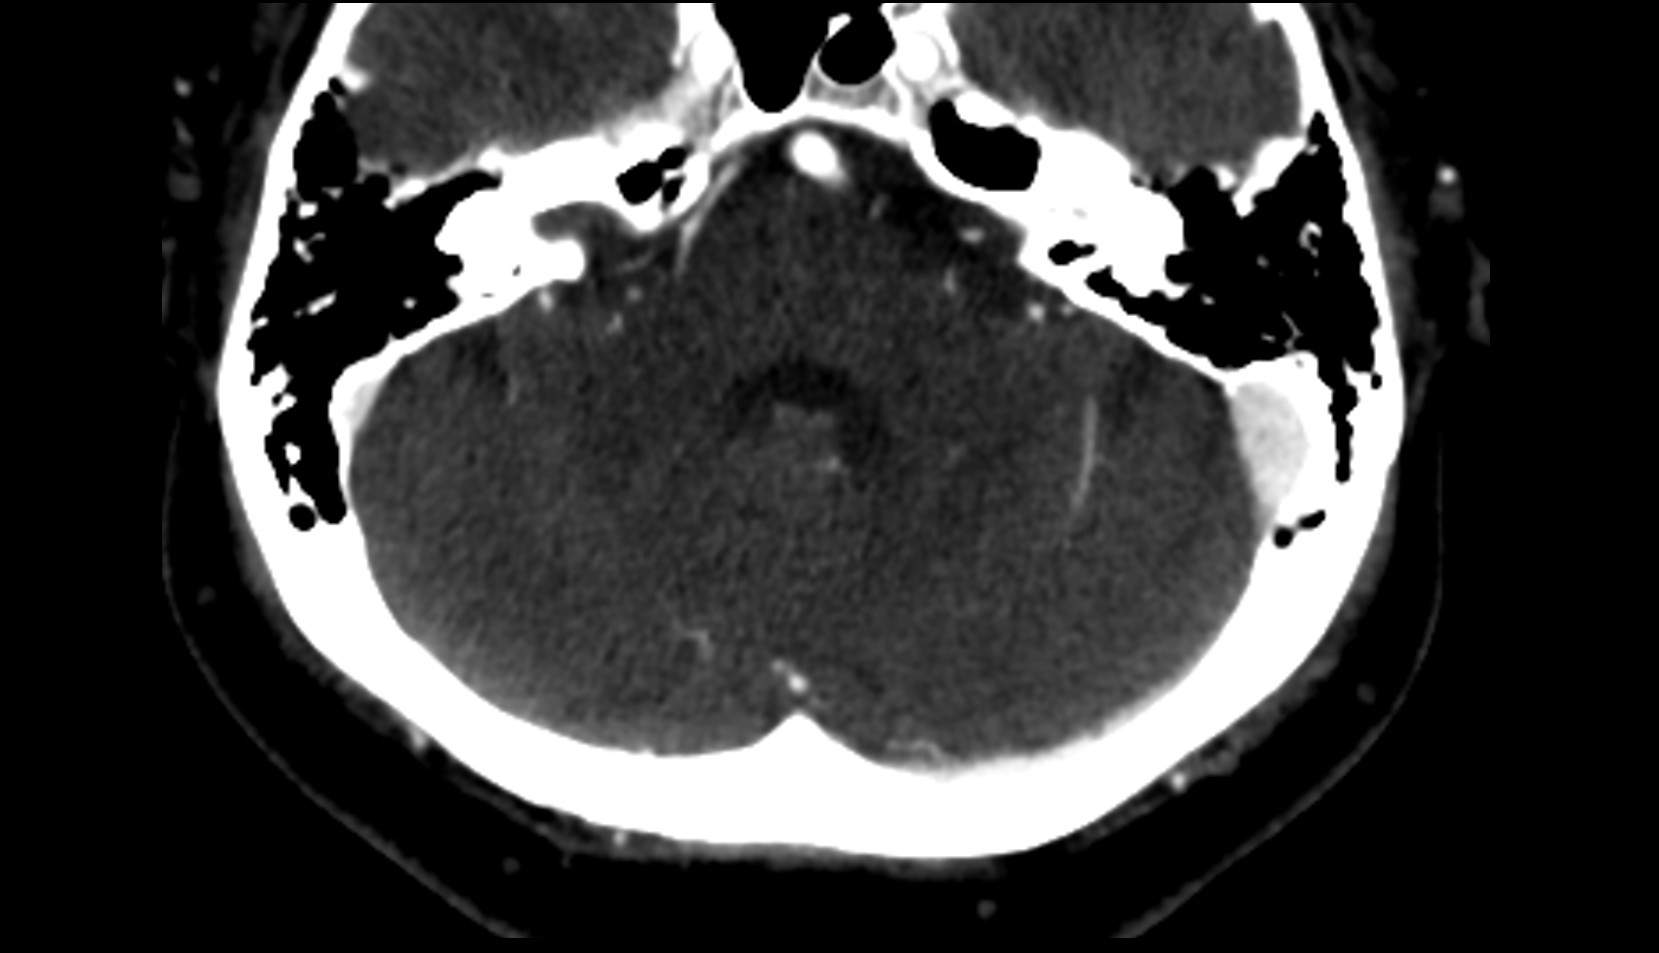

- Cerebellum